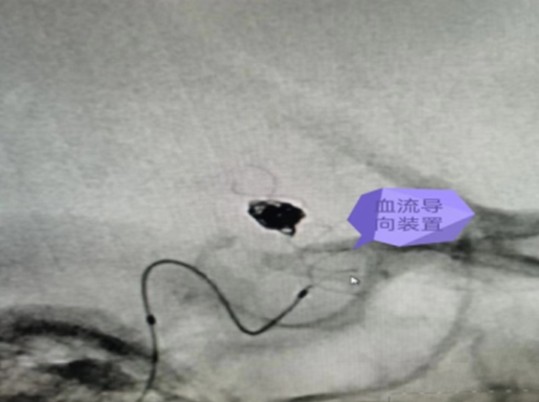

我院成功完成一例顱內(nèi)血泡樣動脈瘤血流導(dǎo)向裝置植入彈簧圈栓塞手術(shù)

通訊員周利軍報:近日,衡陽市中心醫(yī)院神經(jīng)外科團(tuán)隊成功完成一例顱內(nèi)血泡樣動脈瘤血流導(dǎo)向裝置植入+彈簧圈栓塞手術(shù),術(shù)后患者恢復(fù)良好,術(shù)后10天復(fù)查腦血管造影提示動脈瘤未見未顯影,患者住院16天康復(fù)出院。該手術(shù)標(biāo)志該院神經(jīng)外科團(tuán)隊顱內(nèi)動脈瘤的介入治療技術(shù)邁入一個新的高度。

衡陽市中心醫(yī)院神經(jīng)外科主任李遠(yuǎn)志緊急組織醫(yī)師團(tuán)隊開展術(shù)前討論,分析認(rèn)為結(jié)合該動脈瘤的形態(tài)及部位等特點,診斷為右側(cè)后交通段血泡樣動脈瘤,再次破裂風(fēng)險極高,建議積極手術(shù)治療。手術(shù)開顱夾閉手術(shù)風(fēng)險高,難度大,而常規(guī)支架輔助+彈簧圈栓塞后期動脈瘤進(jìn)展及復(fù)發(fā)可能性高。較好的治理方式為血流導(dǎo)向裝置置入+彈簧圈栓塞治療,并取得家屬同意。

7月14日,在麻醉科及介入手術(shù)室的密切配合下,神經(jīng)外科醫(yī)師團(tuán)隊順利完成了此例后交通段血泡樣動脈瘤血流導(dǎo)向裝置+彈簧圈栓塞手術(shù),拆除了龍女士腦子里的“不定時炸彈”。

據(jù)悉,顱內(nèi)血流裝置(PED)是一種治療顱內(nèi)復(fù)雜動脈瘤新型的治療方式,通過置入所到病變動脈后,使動脈內(nèi)的血流動力學(xué)發(fā)生改變,緩慢的在動脈瘤內(nèi)形成血栓,內(nèi)膜上皮攀爬到支架表面從而來修復(fù)病變血管使其發(fā)生血管重建來修復(fù)病變的載瘤動脈。血流導(dǎo)向裝置的發(fā)展更新了動脈瘤的治療理念,對顱內(nèi)復(fù)雜動脈瘤的治療結(jié)果產(chǎn)生革命性的變化,具有手術(shù)微創(chuàng),操作簡單,安全性相對較高,在降低動脈瘤復(fù)發(fā)方面更具有優(yōu)勢。